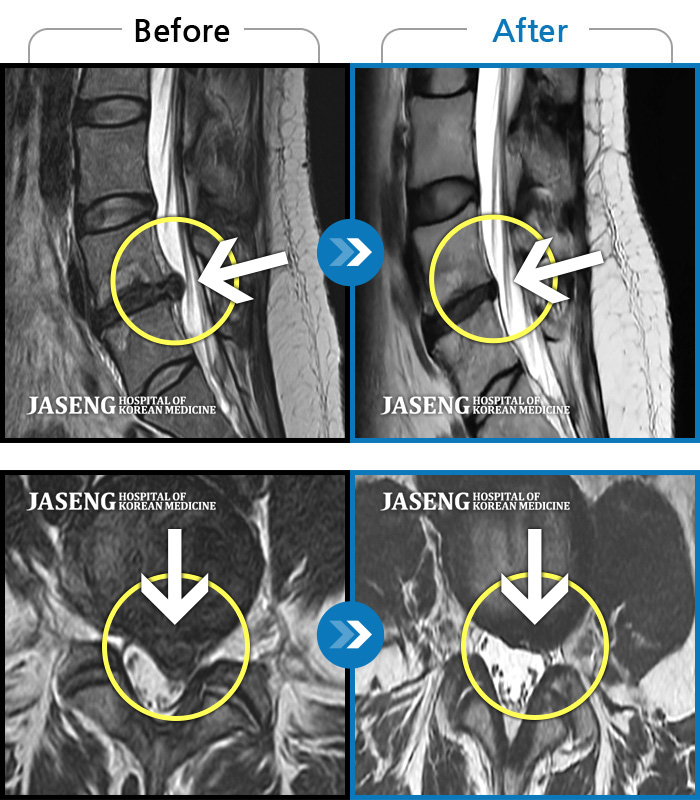

Before

After

환자에게 사전 동의를 받아 동일 조건에서 촬영되었습니다.

개인에 따라 치료 후 부작용이 발생할 수 있으니 의료진과 상담 후 치료를 진행하시기 바랍니다.

디스크 탈출로 인한 근력저하 및 감각저하

허리통증으로 보행 불가. 우측 다리의 통증과 저림, 화끈거리는 통증과 차가운 느낌 번갈아 나타남